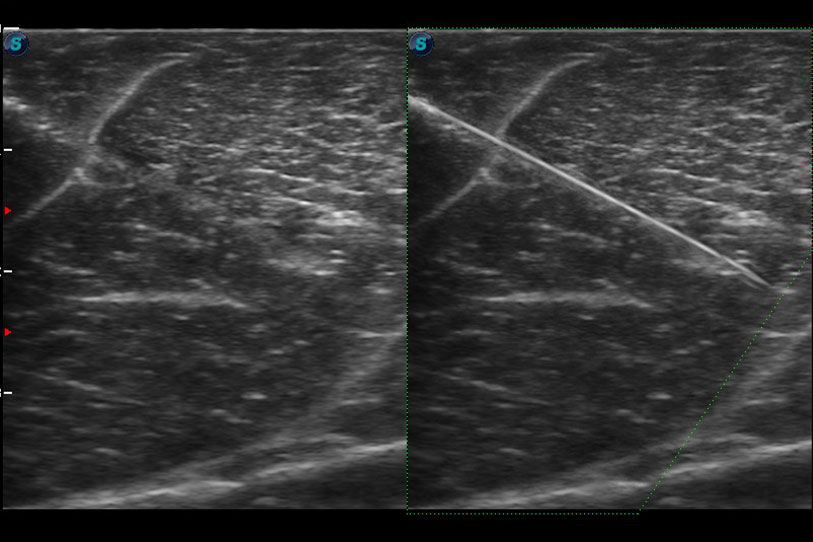

增強(qiáng)穿刺針在動(dòng)物解剖結(jié)構(gòu)中的位置,提高穿刺介入的安全性和準(zhǔn)確性。

ProPet 70 進(jìn)一步提升了微米成像算法,更加注重對(duì)基礎(chǔ)原始圖像的還原和保留,在有效減少斑點(diǎn)噪聲、增強(qiáng)組織邊界顯示的同時(shí),避免過(guò)度優(yōu)化丟失真實(shí)的解剖信息。

為精細(xì)結(jié)構(gòu)及組織邊緣提供高清晰度的圖像和更大的成像視野。幫助減輕醫(yī)生的用眼疲勞,快速精準(zhǔn)獲得測(cè)量的數(shù)據(jù)。